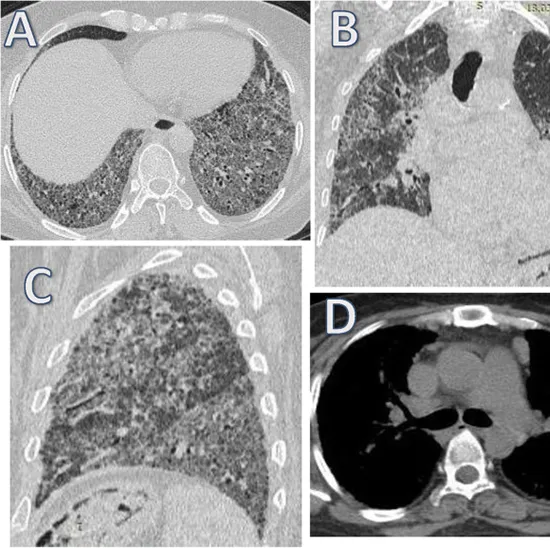

HRCT Lungs, also known as high-resolution CT of the lungs, is used to visualise the detailed structure of the lungs in order to assess diffuse interstitial lung disease.

High-resolution computed tomography (HRCT) is a more precise method of examination than chest 2-rat in the diagnosis and monitoring of lung tissue and airway diseases. A volume HRCT scan of the entire lung tissue is possible with modern CT equipment.